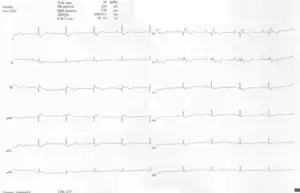

Other abnormalities that can be seen on the ECG include:

1. signs of right atrial enlargement or tall and broad 'Himalayan' P waves

2. first degree atrioventricular block manifesting as a prolonged PR-interval[5]

3. low amplitude QRS complexes in the right precordial leads

4. atypical right bundle branch block

5. T wave inversion in V1-V4 and Q waves in V1-V4 and II, III and aVF.[6]